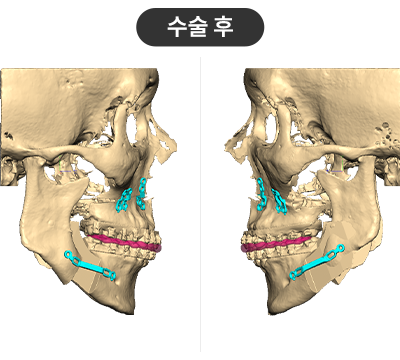

STEP 01

3D플랜에 따라 최적의 위치로 상-하악을 위치시킴

STEP 02

무턱 교정을 위해 하악을 앞으로 이동시켜 적정한 교합을 맞춤

STEP 03

플랜을 기반으로 제작된 Wafer를 장착하고 뼈를 고정

수술결과

무턱 개선 : 턱 끝 기준 14mm 전진